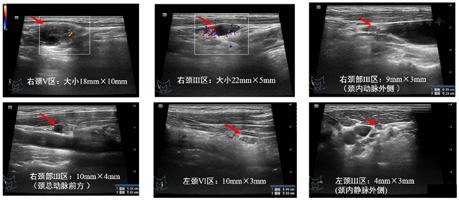

2021年1月20日我院复查超声可见:甲状腺全切术后,右侧颈部Ⅲ区见数处低回声区,大小分别约22 mm×5 mm(内可见局部无回声及结节状高回声,内可见点状强回声)、9 mm×3 mm(颈内动脉外侧)、10 mm×4 mm(颈总动脉前方),右侧颈部V区可见一个混合回声,大小约18 mm×10 mm,左侧颈部Ⅵ区见一处低回声区,大小约10 mm×3 mm,左侧颈部Ⅲ区可见一个低回声,大小约4mm×3mm(颈内静脉外侧)(以上淋巴结超声图像见图1)。左侧颈部Ⅳ见两处低回声区,大小分别约8 mm×5 mm、7 mm×5 mm(颈总动脉与颈内动脉之间,毗邻迷走神经,见图2)。各淋巴结形态尚规则,淋巴门回声消失,CDFI示其内可见点状血流信号。超声提示:甲状腺全切术后,双侧颈部淋巴结肿大伴结构异常,考虑MT。